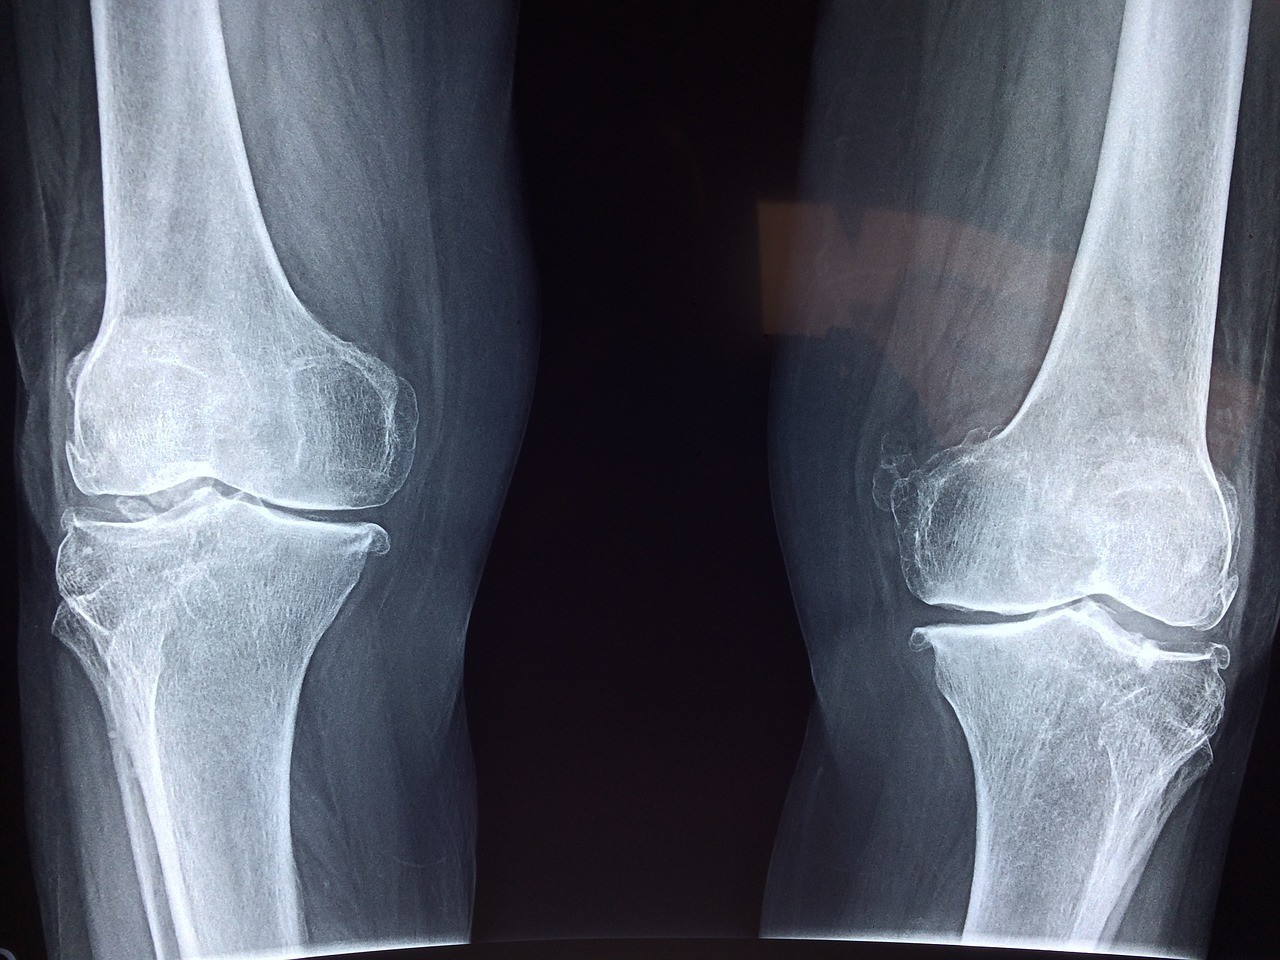

四肢X光

可診斷的疾病:

骨折、關節脫位、關節炎、軟組織損傷等疾病

適合人士:

- 因意外、跌倒、撞擊等導致手臂或腳部疼痛和腫脹的人

- 有關節炎或其他關節疾病的人

- 懷疑自己可能有骨折或骨裂的人

- 懷疑自己可能有骨質疏鬆症的人

- 做運動時感覺到不舒服或疼痛的人

所需時間:

約 15 至 30 分鐘